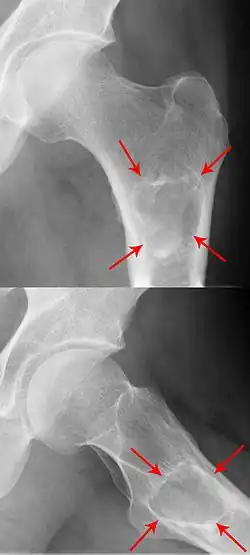

Röntgenbild eines Enchondroms im Ober­schenkel­knochen

kalzifizierendes Enchondrom am distalen Femur

Im Röntgenbild stellt sich das klassische Enchondrom als zur Knochenachse längliche, ovaläre Läsion zentral im Markraum langer Röhrenknochen dar. Eine exzentrische Lage schließt ein Enchondrom jedoch nicht aus. Das Zentrum der Läsion liegt meist in der Metaphyse oder in der distalen Diaphyse eines Röhrenknochens. Ein kleiner oder kurzer Knochen kann vollständig ausgefüllt sein. Typisch für Enchondrome ist eine Ausdünnung der Kortikalis des Knochens von innen, das sogenannte Scalloping und im Falle einer Expansion über das Volumen des Knochens hinaus die Neubildung der Kortikalis (Neocortex). Eine Periostreaktion wird jedoch praktisch nie beobachtet. Das Erscheinungsbild eines Enchondroms wird des Weiteren hauptsächlich vom stark variierenden Ausmaß der Verkalkungen der primär knorpeligen Tumormatrix geprägt: diese können punktförmig, ring- und bogenförmig („rings and arcs“) und flockig sein. Oftmals imponiert das Bild Popcorn-artig. Die Verkalkungen treten häufiger und ausgeprägter in den langen Röhrenknochen auf, während die Läsionen in den kleineren Knochen der Finger und Füße weniger verkalken. Das Röntgen-Bild erfasst sicher nur die Verkalkungen und das Scalloping, so dass das wahre Ausmaß eines nur gering verkalkten Enchondroms mit dieser Methode unterschätzt werden kann. Verschwinden von vormals verkalkten Arealen innerhalb eines Enchondroms im Verlauf muss als Hinweis auf eine Entartung gedeutet werden.[2]